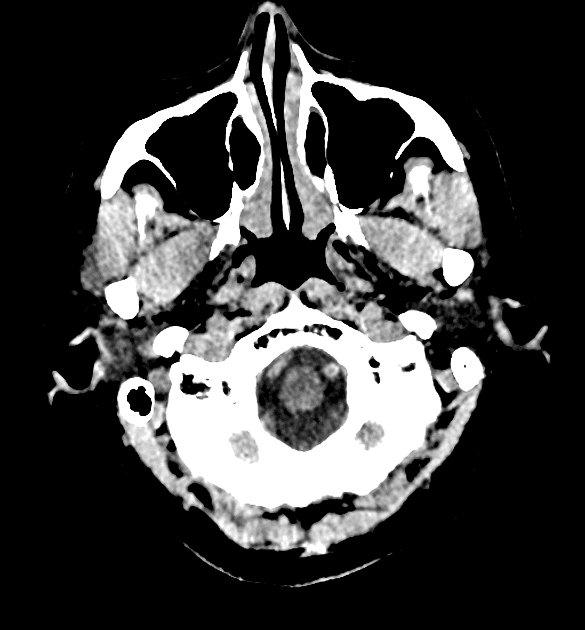

- Khối liên tục với cuống yên, làm giãn cuống này cả phía trên và phía dưới.

- Phù hợp với kiểu tăng quang đặc trưng và nằm trong cuống yên (infundibulum).

- Khối phù hợp với kiểu tăng quang đặc trưng và nằm trong cuống yên (infundibulum).

- Khối liên tục với cuống yên, làm giãn cuống cả phía trên và phía dưới.

- "Đặc điểm hình ảnh gồm khối u ranh giới rõ, tăng quang mạnh, liên tục với và làm giãn cuống yên."

U Pituicytoma là một loại khối u thần kinh đệm lành tính, phát triển chậm và hiếm gặp, xuất phát từ các tế bào pituicyte ở thùy sau tuyến yên hoặc cuống yên. Khối u thường biểu hiện như một tổn thương ranh giới rõ, tăng quang mạnh và liên tục với, đồng thời làm giãn cuống yên. Trên cộng hưởng từ (MRI), khối u thường có tín hiệu đẳng trên hình ảnh T1 và tăng quang đồng nhất sau khi tiêm thuốc cản quang. Việc không có dấu hiệu ác tính, không bệnh toàn thân và tổn thương ổn định dài hạn trên hình ảnh học làm tăng khả năng chẩn đoán u Pituicytoma, ngay cả khi chưa xác định bằng mô bệnh học. Các chẩn đoán phân biệt bao gồm u tuyến yên có liên quan đến cuống yên, u màng não và bệnh tổ chức bào Langerhans, những bệnh này có thể có hình ảnh tương tự. Tuy nhiên, vị trí đặc hiệu trong cuống yên và sự liên tục với cuống làm nghiêng về chẩn đoán u Pituicytoma. Điều trị thường mang tính theo dõi bảo tồn, đặc biệt ở bệnh nhân không có triệu chứng.